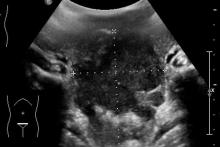

Rozpoznanie: W badaniu USG uwidoczniono w jamie brzusznej rozległe masy guzowate (pomiary między kursorami). Skierowany do dalszej diagnostyki.